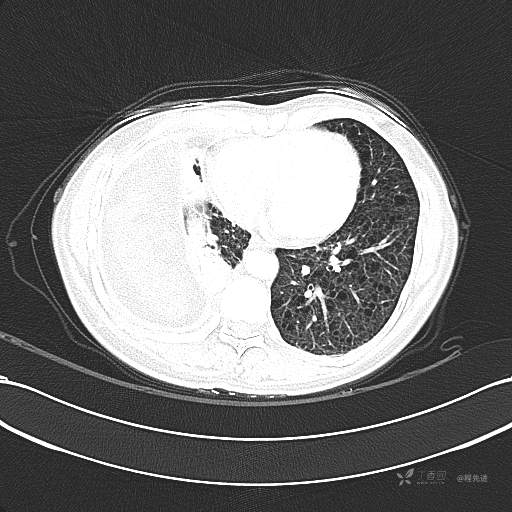

患者性别:女

患者年龄:51岁

简要病史:胸闷半年